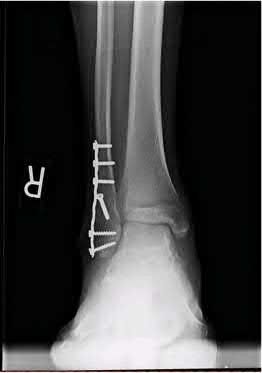

A 64-year-old woman is thrown off a horse, sustaining the injury shown in Figures A and B. She undergoes surgical fixation as seen in Figures C through E. What is the most commonly reported complication of this procedure?

The patient in the scenario has a 2-part proximal humerus fracture treated with a locking plate as seen in Figures A-E. The most common complication with the use of this implant is screw penetration. The terms screw cut out and penetration are often used interchangeably in the literature with cut out appearing more frequently in reports regarding intertrochanteric fractures.

Owsley et al retrospectively reviewed 53 proximal humerus fractures treated with locking plates and the same post-operative protocol. The most common complication was screw cut out or penetration, followed by varus displacement. They concluded that 3 and 4-part fractures in patients over 60 years have a higher incidence of failure.

Agudelo et al retrospectively reviewed 153 patients at a level-one trauma center treated with proximal humerus locking plates, investigating modes of failure for the implant. They determined that varus malreduction (head-shaft angle